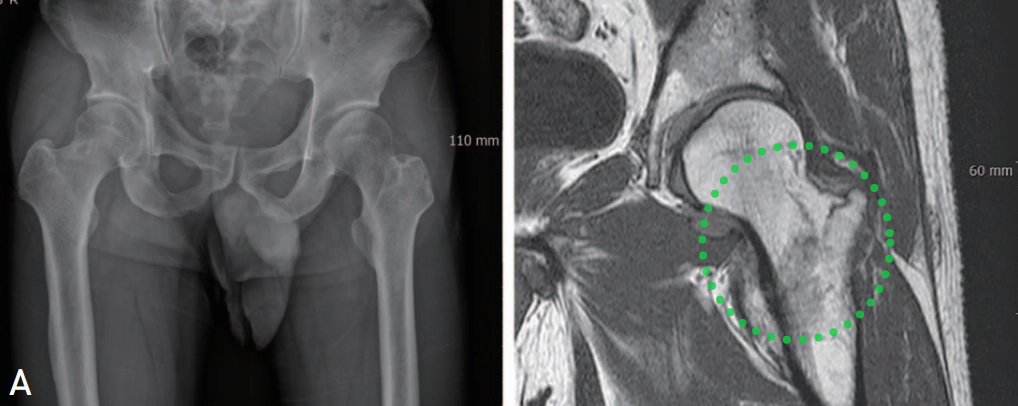

▲图示可见做侧转子间骨折线累及整个大小转子间骨质,且累及股骨颈基底部。

7例同时行CT和磁共振检查的患者中,3例CT提示为孤立性大转子骨折,但磁共振显示所有7例患者的骨折均延伸至转子间内侧1/2皮质,其中4例接受了手术治疗。